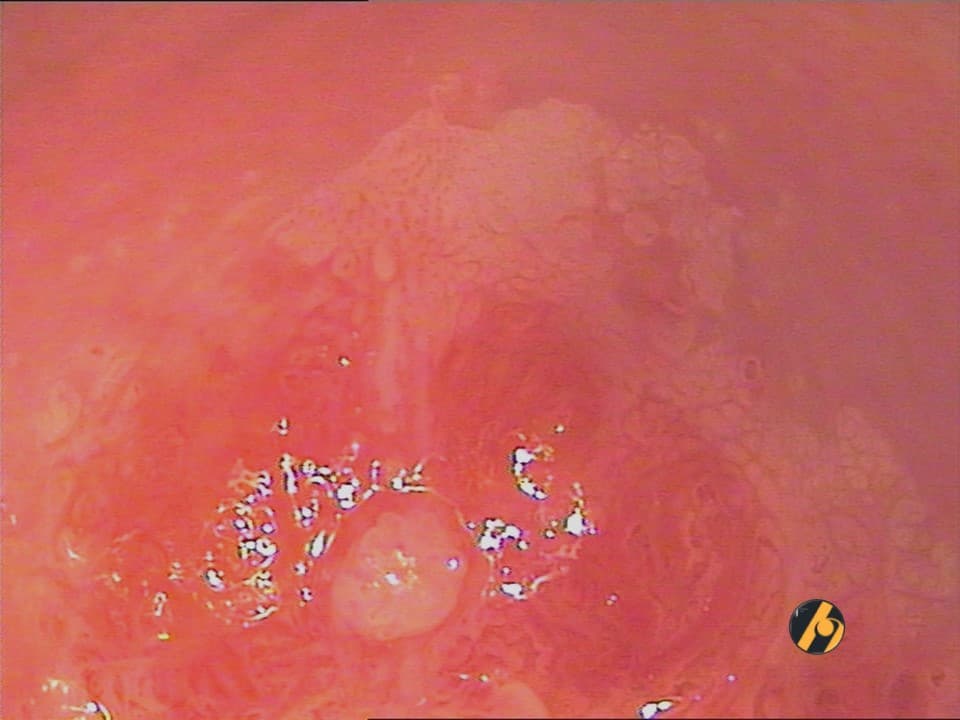

Punktacije i mozaik predstavljaju vaskularne fenomene, koji se uočavaju nakon nanošenja octene kiseline, dok su tek u pojedinačnim slučajevima vidljivi pri većim povećanjima i uporabi zelenog filtera kod nativne kolposkopije. Najvažniji kriteriji u kolposkopskoj procjeni punktacija su kvalitet kapilarnog crteža kao i interkapilarni razmak. Kao i kod nježnog acetobijeljenja, pravilne punktacije se nalaze u slučaju metaplastičnog i akantotičnog benignog epitela te kod skvamozne intraepitelne lezije slabog stupnja. Slika nježnih i pravilnih punktacija nalazi se često u mlađih žena s ovarijskom insuficijencijom, u pacijentica na oralnoj hormonskoj kontracepciji i kod atrofije.